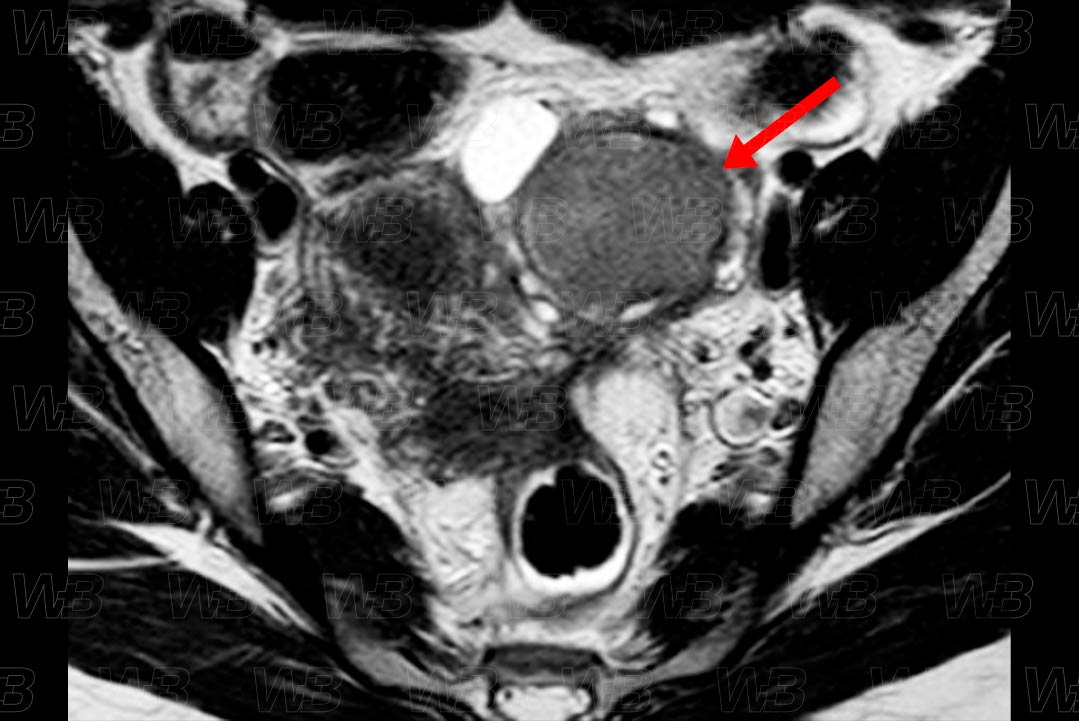

Texto alternativo para a imagem Figura 1. Crédito: Dra. Elazir Mota - Rio de Janeiro/RJ

Descrição da lesão: Ressonância magnética da pelve feminina, estudo coronal (figura 1) e axial (figura 2) em T2, evidenciando volumoso endometrioma no ovário esquerdo, bastante hipointenso em T2, configurando shading .

• Ressonância magnética da pelve: P rincipal exame de imagem a ser solicitado, diante da suspeita clínica. O protocolo utilizado deve incluir estudo T1 no plano axial e sagital. Realizar um pulso de saturação de gordura, deve ser acrescentado para auxiliar na identificação de focos endometriais com conteúdo hemático. O sinal na sequência T2 é variável. O gadolínio não acrescenta grandes informações. Vale destacar que os endometriomas geralmente, surgem como lesões hiperintensas em T1 e predominantemente, hipointensas nas imagens em T2 (aspecto denominado em sombra - shading ).